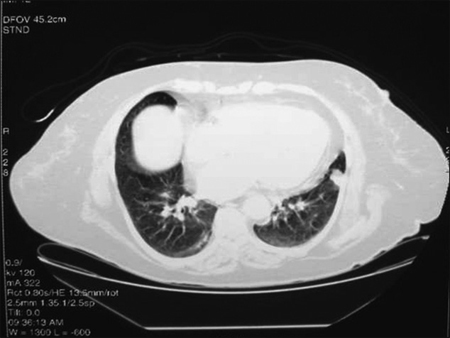

Mujer de 63 años, con antecedentes de tabaquismo crónico (30 paquete/año), depresión mayor y enfermedad pulmonar obstructiva crónica diagnosticada dos meses previo al ingreso. Consultó por 3 meses de tos con estrías de sangre, disnea progresiva y baja de peso de 9 kilos. Además refería poliuria, polidipsia y polifagia. Al momento del ingreso se presentó con apremio respiratorio, taquipnea y uso de musculatura accesoria. En el examen físico destacaba disminución del murmullo pulmonar en la base del hemicampo izquierdo y sibilancias bilaterales. Exámenes de laboratorio iniciales: glicemia 382 mg/dl, kalemia 2,9 mEq/L y alcalosis metabólica no compensada, resto de exámenes normales. La radiografía de tórax mostraba una atelectasia masiva del pulmón izquierdo. En el TC de tórax se observó una lesión pulmonar de aspecto tumoral hiliar izquierda con una gran atelectasia postobstructiva y derrame pleural ipsilateral (Figura 2). La biopsia por fibrobroncoscopía informó un cáncer pulmonar de células pequeñas. Durante la hospitalización se logró un buen control de los síntomas respiratorios; sin embargo, la paciente evolucionó con severas alteraciones hidroelectrolíticas e hiperglicemia resistente al manejo con dosis crecientes de insulina. Se planteó la presencia de un síndrome de Cushing paraneoplásico, por lo que se midió cortisol plasmático matinal: 67 μg/dL (VN < 25), Cortisol libre urinario 24 h = 21.411 μg/24 h (VN = 9-110), ACTH = 100 pg/ml (20-60).

Figura 2